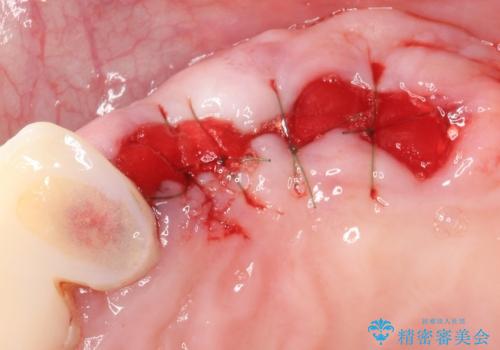

精査したところ、歯周病に罹患した歯を長年放置したことから骨吸収が進行し、上顎骨の厚みはとても薄くなっていました。

全顎的な歯周病治療を行ったのち、上顎洞底挙上術(上顎骨に骨を増やす手術)を併用したインプラント埋入を行いました。